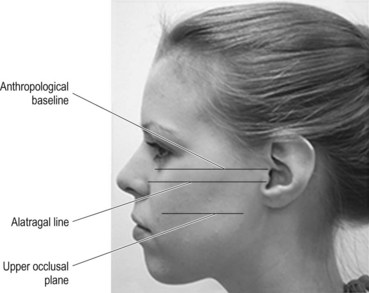

Ala tragus line panoramic. Ikfanson hing university of alabama scho. An imaginary plane or line from the orbital ridge to the acoustic. An imaginary plane or line from the ala of the nose. The roots of the anterior teeth are in the image and the posterior teeth are the same size on each.

Tragus of the ear must be aligned with the plastic guides ala tragus line should be 50 from level positioning the patient position the patient panoramic lead apron must be used position apron high in front to protect the thyroid apron should be lower in back to expose the neck. Discussion most panoramic x ray machines use the ala tragus line for patient positioning whereas a few use the orbito meatal line. Ala tragus line is one of the common extra oral soft tissue land mark utilized in dental clinics for occlusal plane orientation. Here the occlusal plane should be mildly curved upward to make a smile like line.

The ala tragus line as a guide for orientation of the occlusal plane in complete dentures 1carole abi ghosn 2carla zogheib. The smile line will also be lost. An imaginary plane or line from the ala of the nose to the tragus of the ear. The part of a panoramic x ray machine where the cassette is positioned for exposure.

The angle between this line and the horizontal plane is 3on the panorex and 4on the. Focal trough layer that area between the x ray source and the image receptor that will be imaged distinctly on the panoramic. In other words the ala of the nose should be slightly inferior to the height of the tragus. These zones are as follows.

Important in determining the correct position of the patient s head. Exposure was 80 to 90 kv at 10 ma for 1 5 to 2 seconds in accordance with the subject s physical. The panorex i s. To achieve the correct vertical angulation the head must be positioned upright and symmetrical with the ala of the nose just inferior to the height of the tragus.